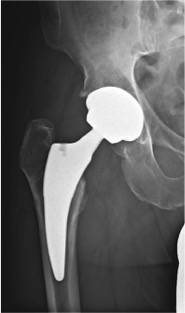

Das Röntgenbild zeigt eine eingesetzte Kurzschaftprothese.